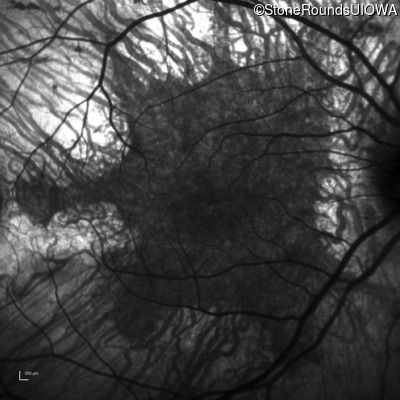

Infrared Fundus Photograph - Right - 20/32

Exemplar